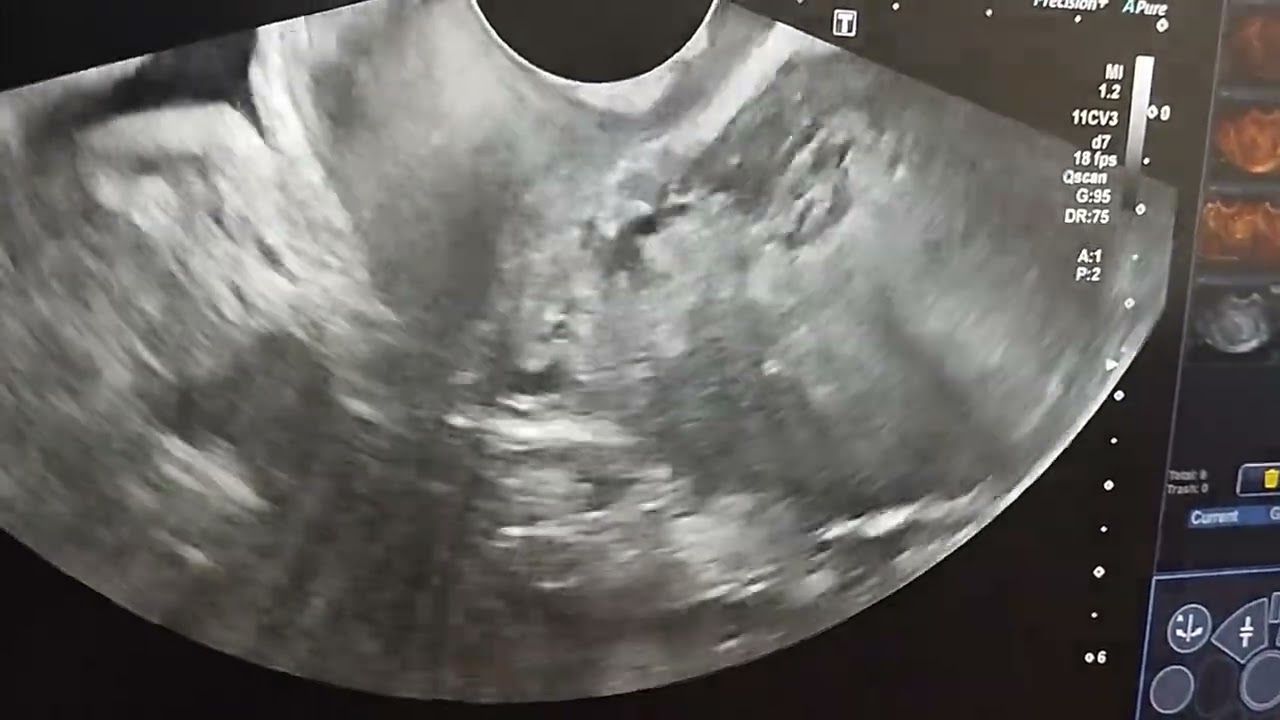

Hematosalpinx

Findings: TVS shows:

1. thick walled elongated cystic structure containing collection with internal echoes and avascular solid component

2. Incomplete septation

3. Mild peripheral vascularity.